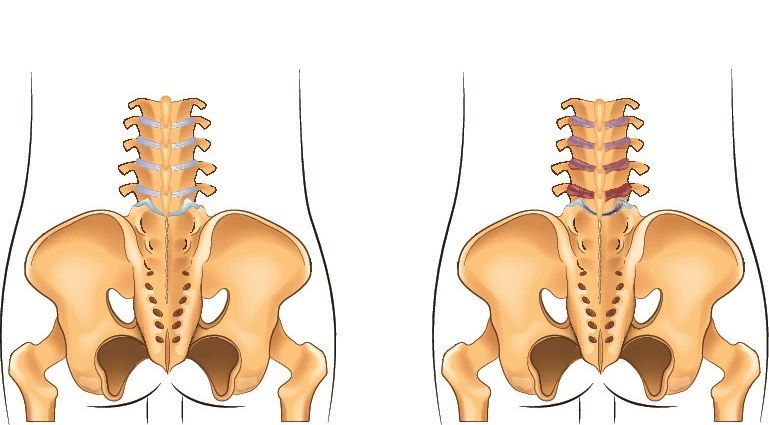

Delays in diagnosing axSpA are troubling, write the authors of a report in the journal Rheumatology. Delays of up to 10 years have been reported. Not all physicians may be familiar with the signs and symptoms of axSpA.

T1-weighted MRI may be a highly specific and reliable test for diagnosing SpA.

Recent studies assessed the impact of statins on disease activity and compared plain radiography vs MRI for early diagnosis of axSpA.